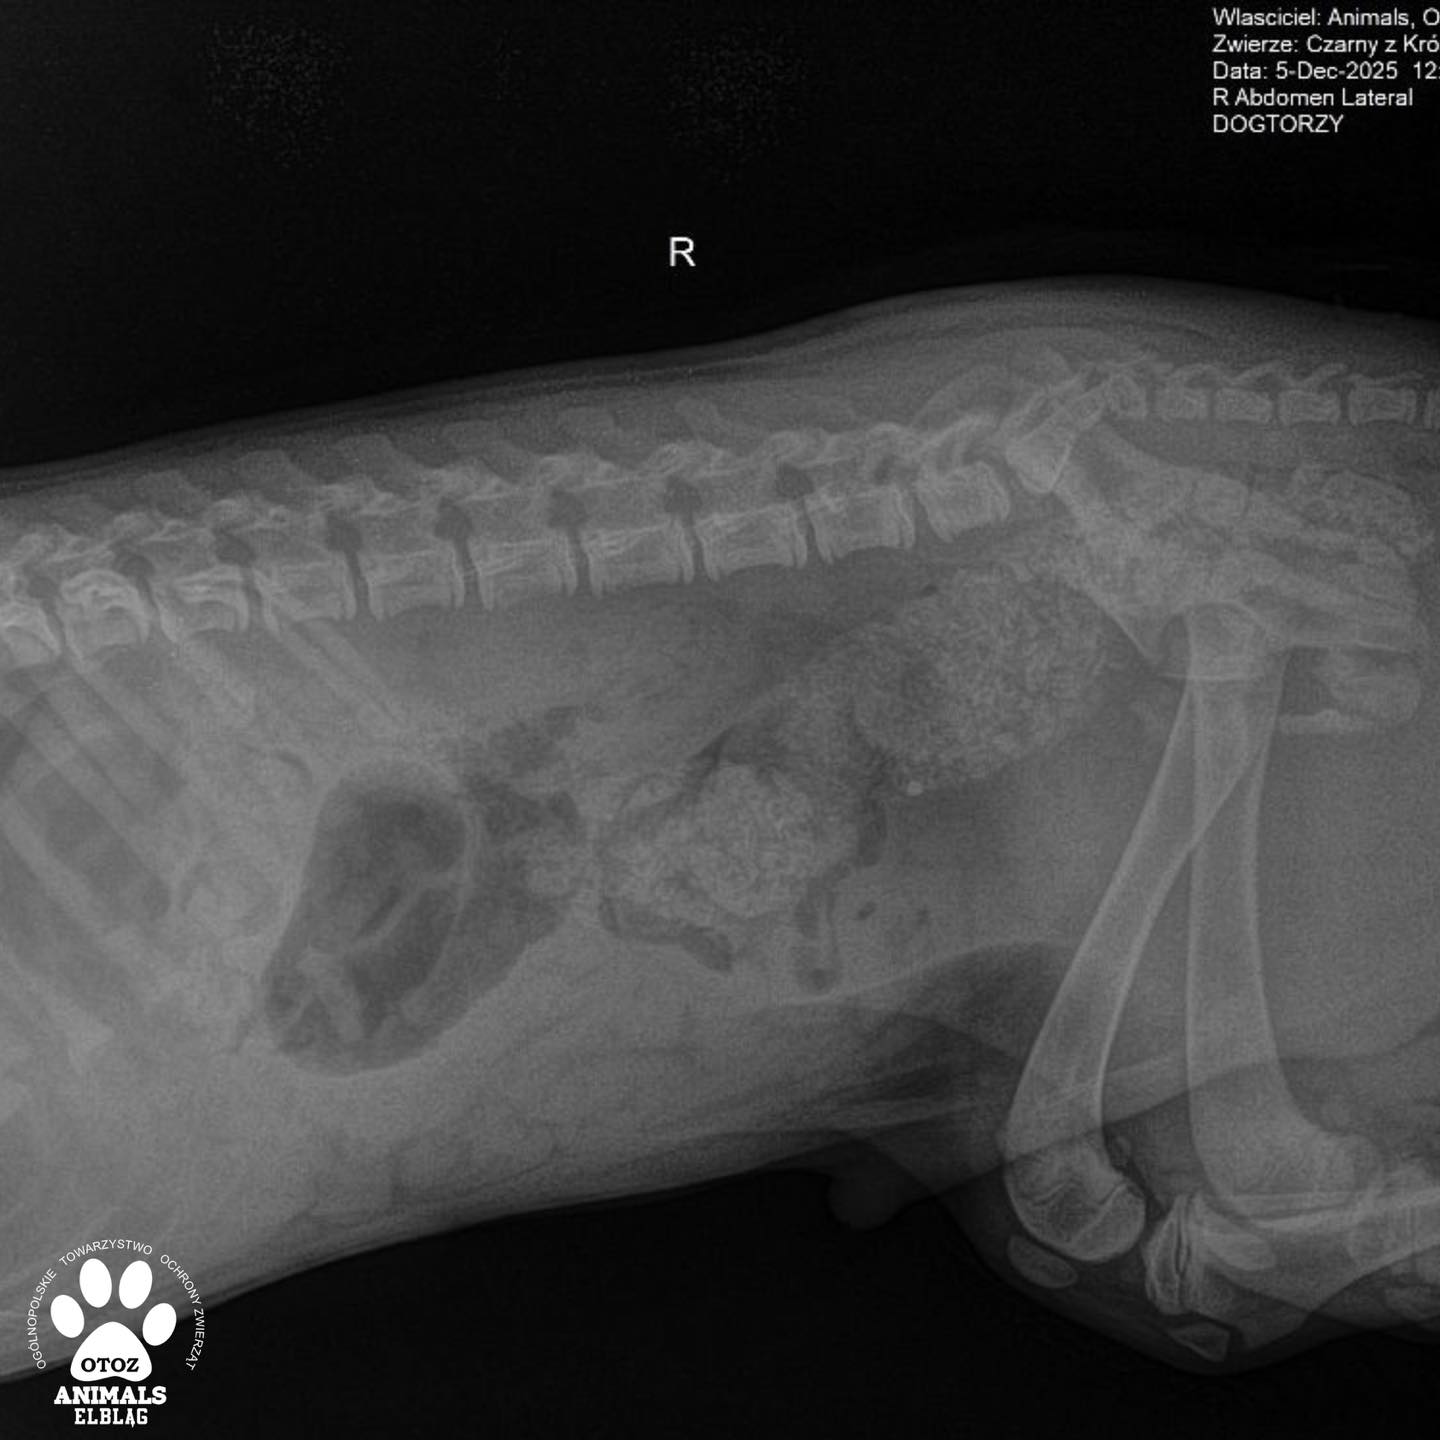

Suczka Nastka jest już po operacji. Jej życiu nie zagraża już niebezpieczeństwo - dochodzi do zdrowia w schroniskowej izolatce. Will w wyniku wypadku komunikacyjnego doznał złamania kości biodrowej, łonowej i kulszowej.

Dzisiaj czeka go bardzo poważny zabieg - osteosynteza z użyciem płyty. Koszt tego zabiegu to 3000 zł. Gorąco prosimy Was o pomoc w opłaceniu tej faktury…